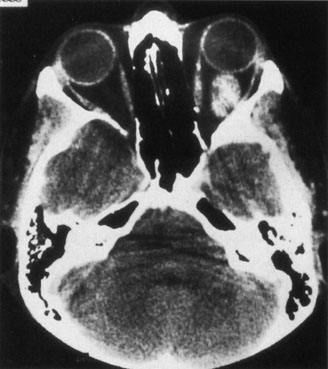

Investigations

Contrast-enhanced CT of the orbits with direct and coronal cuts is the radiologic study of choice for these patients.45 A well-demarcated, encapsulated oval or rounded mass is revealed, which is typically intraconal in the lateral part of the middle third of the orbit (Fig. 5) but occasionally may extend to the extraconal space.42 Septa within the tumor may be apparent on high-resolution CT. The posterior pole of the globe frequently is indented by the rounded anterior margin of the tumor.42 The optic nerve typically is displaced rather than surrounded by the tumor. Subtle outward bowing of the lateral orbital wall or increase in orbital size may be present, consistent with a long-standing, slowly growing mass lesion.10,42 Enhancement with intravenous contrast occurs and may be homogeneous or inhomogeneous.10,45 Rarely, cavernous hemangiomas may occur as an intraosseous tumor within the orbital or facial bones.42,53–55 Although usually an isolated intraorbital lesion, multiple lesions in one orbit occurred in 8 of 164 (5%) patients of three combined large studies,10,42,45 and bilateral multiple cavernous hemangiomas also have been described.56 In contrast to patients with venous flow malformations in which phleboliths are common, phleboliths are rare in cavernous hemangiomas. Three large studies comprising 164 patients with cavernous hemangioma all reported that no calcification was detected within the tumor.10,42,45If the diagnosis is still unclear or if better definition of details and localization of the lesion is required, then MRI should be performed. Magnetic resonance imaging demonstrates nonspecific characteristics of a lesion isointense to muscle and gray matter on T1-weighted images and hyperintense on T2-weighted images (Fig. 6).57 The lesions show initial central patchy enhancement, which fills up homogeneously within 20 to 60 minutes.58 If ultrasonography is performed, B-scan ultrasonography shows a well-circumscribed mass with a sharply defined anterior acoustic border.23 A-scan ultrasonography shows high reflectivity of the echo signals resulting from the multiple blood-filled vascular channels, regular internal structure with a higher anterior and posterior spike marking the capsule, and moderate sound attenuation (angle of decrease of the echo spike within the lesion).24 Arteriography is not indicated.

Fig. 5. Cavernous hemangioma. Contrast-enhanced axial computed tomography scan shows a well-demarcated, oval intraconal mass in the lateral part of the middle third of the orbit. Note the enhancement within the lesion, which in this instance is inhomogeneous, but can also be homogeneous.